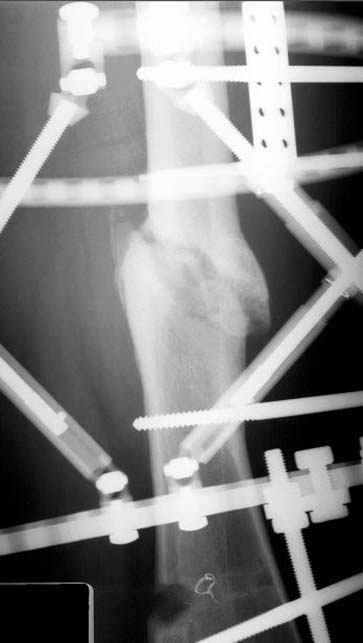

пластическая модель; и коррекция бедра аппаратом Илизарова.

Имею другие снимки тоже, получится как отчет о моей работе.

С уважением Джолдас